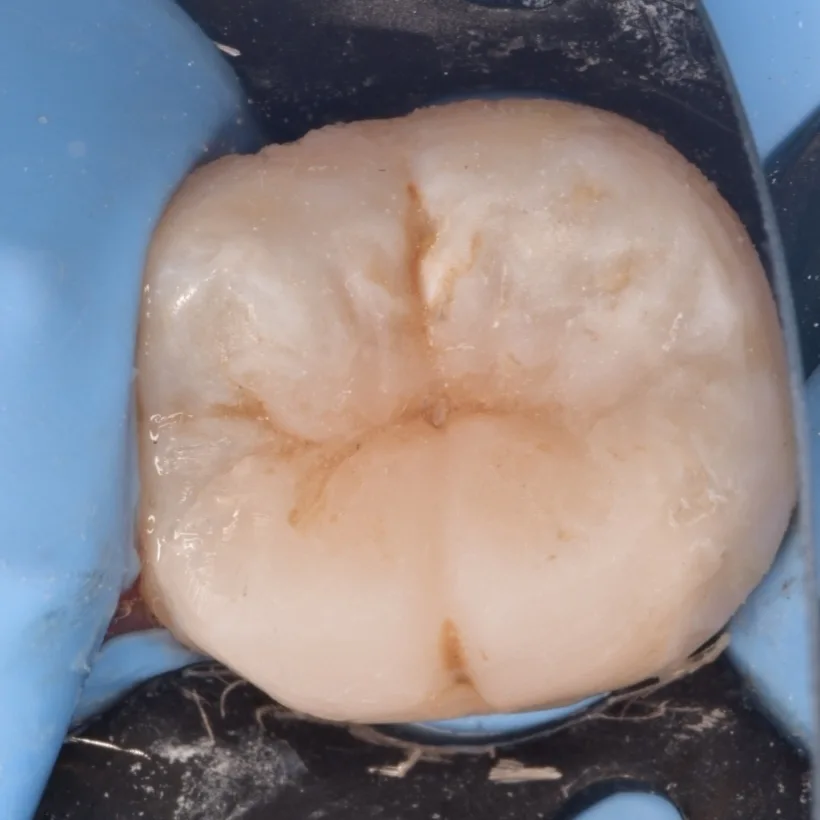

When I reach the IDS step I try fix the isolation problem as could as possible not only sheet and clamp together,

IDS with gold standard SE bond ,RC with flowable composite, Ever X posterior for dentin replacement , this photo shows the beginning of the anatomy 😀

Immediate result